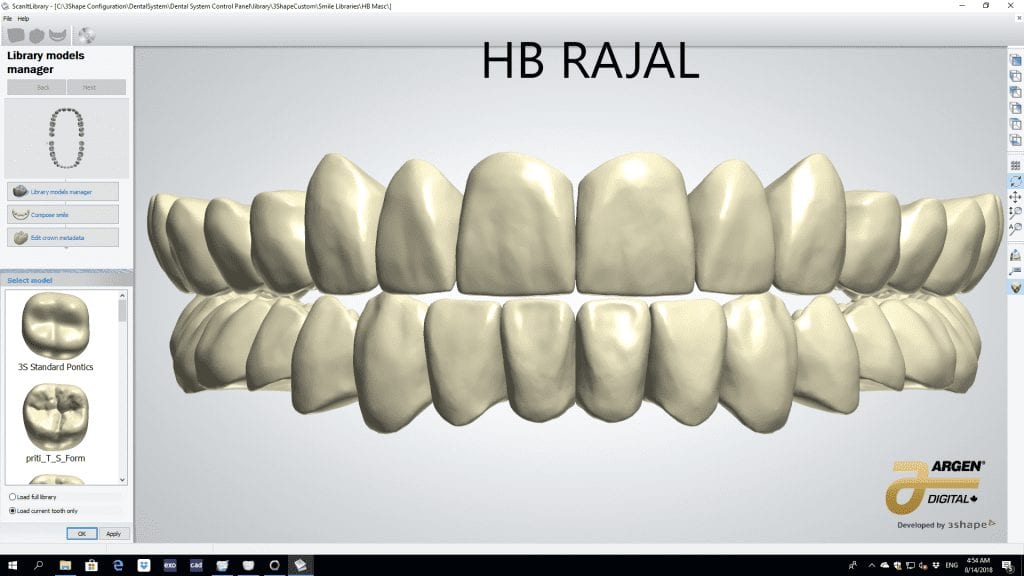

The digital models were then imported into a third party software where a library of tooth morphologies are available for the clinician to choose from.

Once the appropriate library is chosen, the digital wax ups are performed. In the subsequent photos you can see the transparent overlay of the wax-ups to the original position of the existing dentition